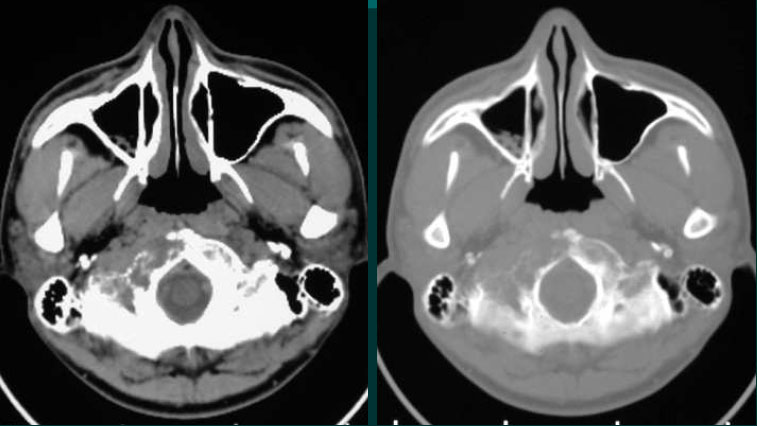

男性,20岁。

颈部疼痛2月,腰部臀部疼痛1月。

The tumor often demonstrated isodensity with patchyhypodensity areas on unenhanced CT images.

On T1WI, the tumor demonstrated isointensity or slightly hypointensity; on T2WI, the tumor demonstrated heterogeneous hyperintensity.

The tumor demonstrated heterogeneous enhancement on contrast-enhanced CT/T1WI.

Calcification is rare.

Cystic necrotic component and haemorrhagic change are usually obvious.